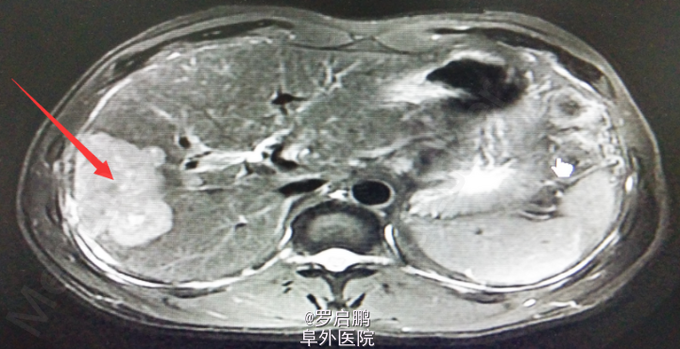

患者 男 48岁 主诉:发现肝脏占位半月 现病史:半月前患者因慢性乙型肝炎复查腹部超声发现右肝占位 既往:慢性乙肝20年,未规律治疗。 个人史:吸烟史25年20支/天,饮酒史13年,白酒2两/次。

超声:右肝高回声光团,胆囊、肝内外胆管、脾脏、双肾未见异常 腹部MRI:肝右叶占位 腹部平扫+增强:肝右叶占位,肝内多发小密度,左肾囊肿,腹膜后淋巴结肿大

肝右叶占位,肝癌? 前入路右半肝切除,LC 鉴别诊断:原发性肝癌;肝转移癌;肝海绵状血管瘤;肝腺瘤;血管平滑肌脂肪瘤。

注意术中循环维持,备血、血浆。术中平稳。术中病理:(右半肝)低分化胆管腺癌,可见坏死,肝内可见多发卫星灶,紧邻肝被膜,切缘未见特殊。术后恢复良好出院。